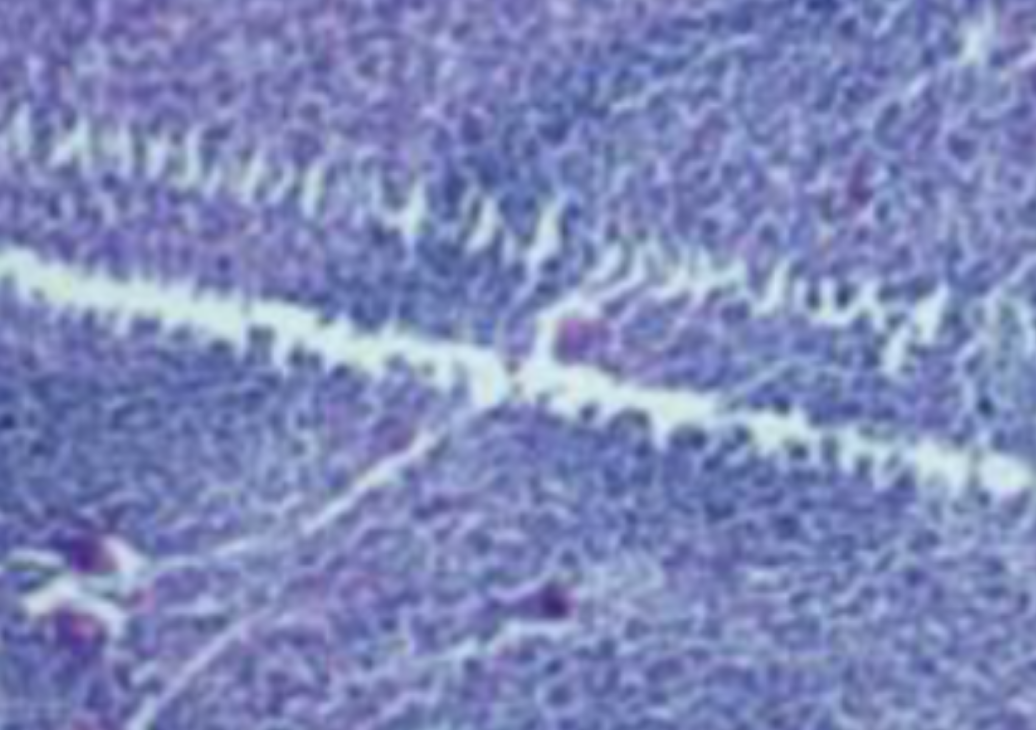

HE染色,全称苏木精-伊红染色法(Hematoxylin and Eosin staining),是最常见的组织切片染色技术之一,用于在显微镜下观察和分析组织或细胞的结构和形态。

虽然HE染色是最常见且最基础的染色技术之一,😭但在实验过程中,很容易出现各种情况导致染色切片质量参差不齐。所以,小编根据以往实验经验,给大家整理归纳出了15个HE染色中的常见问题,还包含问题原因分析以及解决方法哦~